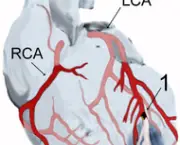

Ataque cardíaco ocorre quando uma artéria coronária se torna bloqueadas de modo simultâneo. O bloqueio repentino rouba certa porção do músculo do coração e fornecimento vital do sangue. De fato acontece a morte do músculo. O bloqueio súbito da artéria coronária é causada por ruptura de placa na artéria que produz variedade de condições clínicas, incluindo ataques cardíacos e angina instável, agrupados sob o nome de síndrome coronariana aguda (SCA). Todas as formas de SCA são emergências médicas, tratados com medicamentos, angioplastia, implante e cirurgia para restaurar o fluxo normal de sangue através da artéria bloqueada. Se o fluxo pode ser restaurado dentro de poucas horas, danos permanentes podem ser minimizados.

Infarto do miocárdio resulta da interrupção parcial do fornecimento de sangue a uma parte do músculo cardíaco, fazendo com que as células do coração sejam danificadas até morrer. Isto acontece em geral devido à oclusão (bloqueio) de uma artéria coronária após a ruptura da placa aterosclerótica vulnerável, conjunto estável de colesterol, ácidos gordos e os glóbulos brancos do sangue na parede da artéria. Resultante de isquemia (restrição no fornecimento de sangue) e consequente falta de oxigênio. Caso deixada sem tratamento por um período de tempo suficiente pode causar danos ou morte (infarto) do tecido muscular do coração (miocárdio). Os sintomas típicos de infarto agudo do miocárdio incluem súbita dor no peito (geralmente irradia para o braço esquerdo ou do lado esquerdo do pescoço), falta-de-ar, náuseas, vômitos, palpitações, sudorese e ansiedade. As mulheres podem experimentar sintomas típicos menores do que os homens, caso da falta de ar, fraqueza, sensação de indigestão e fadiga. Proporção considerável de infartos do miocárdio (22-64%) “silenciosa”, isto é, sem dor no peito ou outros sintomas. Entre os testes de diagnóstico para a detecção de danos ao músculo cardíaco estão: Eletrocardiograma (ECG), ecocardiograma e vários exames de sangue. Os marcadores utilizados com frequência são de creatina e fração dos níveis de troponina.

- Transmural: Associado com a aterosclerose envolvendo a artéria coronária principal. Prolongam-se através de toda a espessura do músculo cardíaco. Representa resultado da oclusão do fornecimento de sangue da região.

- Subendocárdica: Envolve pequena área na parede subendocárdica do ventrículo esquerdo, septo ventricular ou músculos papilares. A área é susceptível à isquemia.